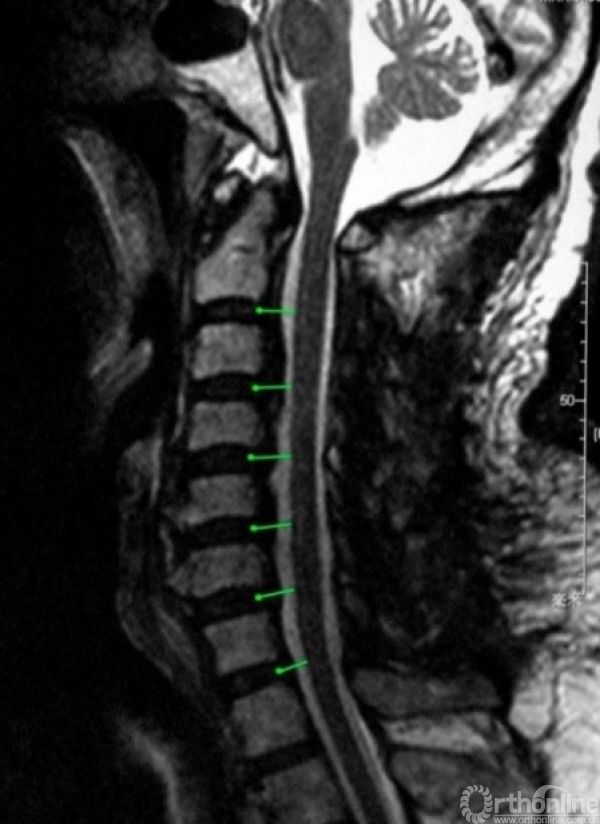

系列研究(四)

当后纵韧带骨化延伸至齿突或寰椎水平时,后路手术往往是唯一的选择。此时,是否有必要做寰椎区域的减压?以往的文献对此研究较少,大多根据个人经验提出倾向性建议:以“弓弦原理”为指导,多认为寰椎后弓切除可能有利于脊髓的整体后移;以“压迫在哪里,就在哪里减压”为原则,多根据椎管狭窄的范围是否包括寰椎来决定是否行寰椎减压。

然而,根据本系列研究的前三部分的结果,后路手术的间接减压效果与减压范围有关:有时减压范围需要大于脊髓受压的范围以获得更好的减压效果,而且这种由于扩大减压范围所产生的额外减压效果仅惠及邻近节段,不会影响远隔节段。但是,寰椎后弓切除的减压效果是否也遵循这一规律,仍需进一步的定量研究加以证实。

此外,尽管寰椎后弓并无重要的肌肉或韧带附着,对颈椎的稳定并无重要作用,但是寰椎后弓的显露和切除过程仍有椎动脉损伤的风险,不宜过于随意,应有明确的指征。所以比较寰椎后弓切除抑或保留对于减压效果的影响具有重要的临床意义,有助于上述指征的确立。

于是,我们回顾性分析了45例含上颈椎后路减压的压迫性颈脊髓病患者的临床资料,按减压范围分为C2-7组(25例)和C1-7组(20例)。利用本系列研究第三部分建立的方法,对两组各个节段的椎髓间距(VCD)进行测量和比较。与之前的研究不同的是,为了避免由于上颈椎形态不规则对测量造成的影响,将参数测量方法人为的标准化,称为标准化椎髓间距(standardized vertebral -cord distance, SVCD),并对测量位点进行了细化,增加了寰椎水平的数据(记为SVCD-C1)、枢椎齿突与枢椎椎体结合部的数据(记为SVCD-C1/2)、枢椎椎体中部水平的数据(记为SVCD-C2)(图1)。并对各个节段的SVCD进行组间比较。

图1

结果显示不仅在C1水平,C1-2及C2水平的SVCD在两组间也有显著差异(图2)。而在C2/3及以下节段,两组间均无显著差异。也就是说,在C2-7减压的基础上切除寰椎后弓,因此而减压效果获益的区域仅限于C1至C2椎体中部区域(图3),无助于C2/3及以下节段减压效果的提高。

图2

图3

通过正态性检验,我们还可以进一步估算两组在C1/2及C2水平致压物大小与压迫残留几率的关系,选择合理的临界值。在C1/2水平致压物矢状径为8.5mm时,C2-7减压在该水平压迫残留率为54.70%,C1-7减压在该水平压迫残留率降低至16.26%;C2水平致压物矢状径为8.5mm时,C2-7与C1-7减压在该水平压迫残留率分别为57.76%与28.82%。

寰椎后弓切除显著提高了颈后路手术在上述测量水平的减压效果。8.5mm可作为在C1/2和C2水平致压物矢状径的临界值。当致压物在C1/2或C2水平超过8.5mm时,即使在寰椎水平无脊髓受压,仍建议向头侧扩大减压切除寰椎后弓,以获得更好的减压效果。

当OPLL累及上颈椎时,需要权衡是否需要切除C1后弓的情况并不少见,本研究有助于合理确定寰椎后弓切除的指征。除了寰椎水平脊髓腹侧(如颈椎后纵韧带骨化延伸至寰椎前弓)或背侧(寰椎后弓发育不良或畸形)存在压迫这一常见手术指征,在寰椎至枢椎体中部范围内,当致压物的矢状径超过采用C2-7减压能获得的SVCD(8.5mm)时,向头端扩大减压,行寰椎后弓切除是获得充分减压的有效手段(图4)。

图4